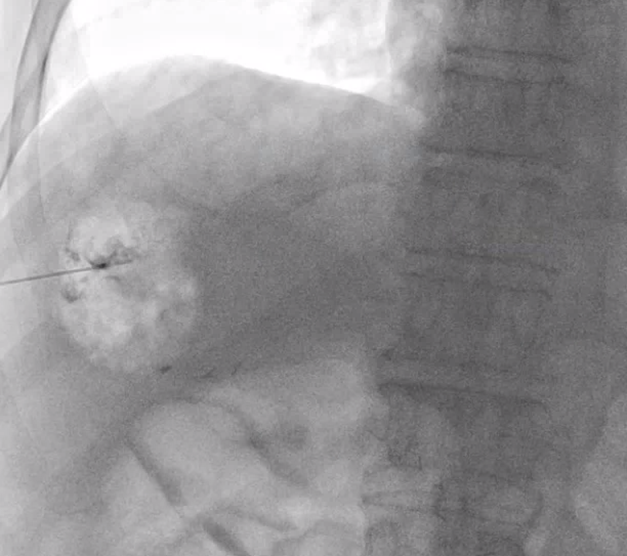

이 바늘은 뚜껑같은 게 있어서 찌르고 난 뒤에 바늘 구멍을 통해 조영제를 주입할 수도 있고 매우 가느다란 철사(와이어)를 넣을 수도 있습니다.

그래서 바늘의 뒷 부분 뚜껑을 열고 조영제를 조금 주입해서 바늘이 목표한 병변 안으로 들어갔는지 확인합니다.

잘 들어갔다는 게 확인되면 아주 가느다란 철사를 넣습니다. 이 철사의 이름은 hair wire 입니다. 마치 머리카락 처럼 가느다랗기 때문이죠.

hair wire 를 넣은 뒤에는 introducer sheath 그 다음엔 앞서 말한 hair wire 보다 조금 굵은 철사가 들어갑니다.